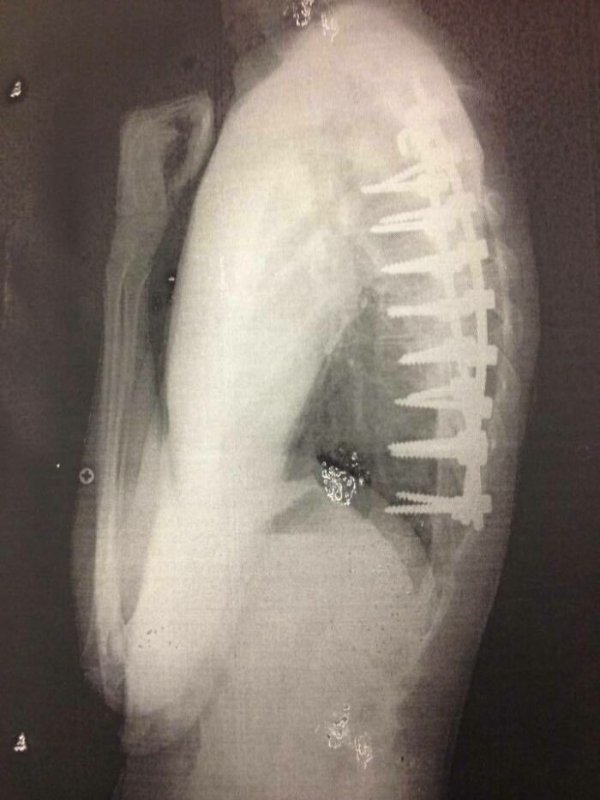

Fascinating Medical Photos